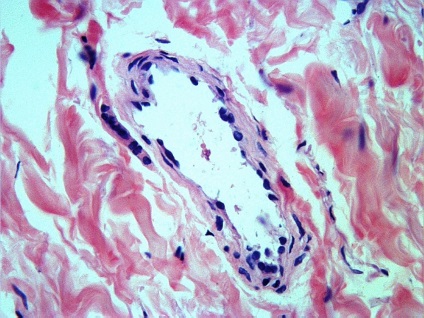

Ábra. 5 érelváltozások a bőr - egy jelzés a biopszia dermatomá

Ábra. 6,7,8 érelváltozások a bőr - jelzi biopszia a bőr graft